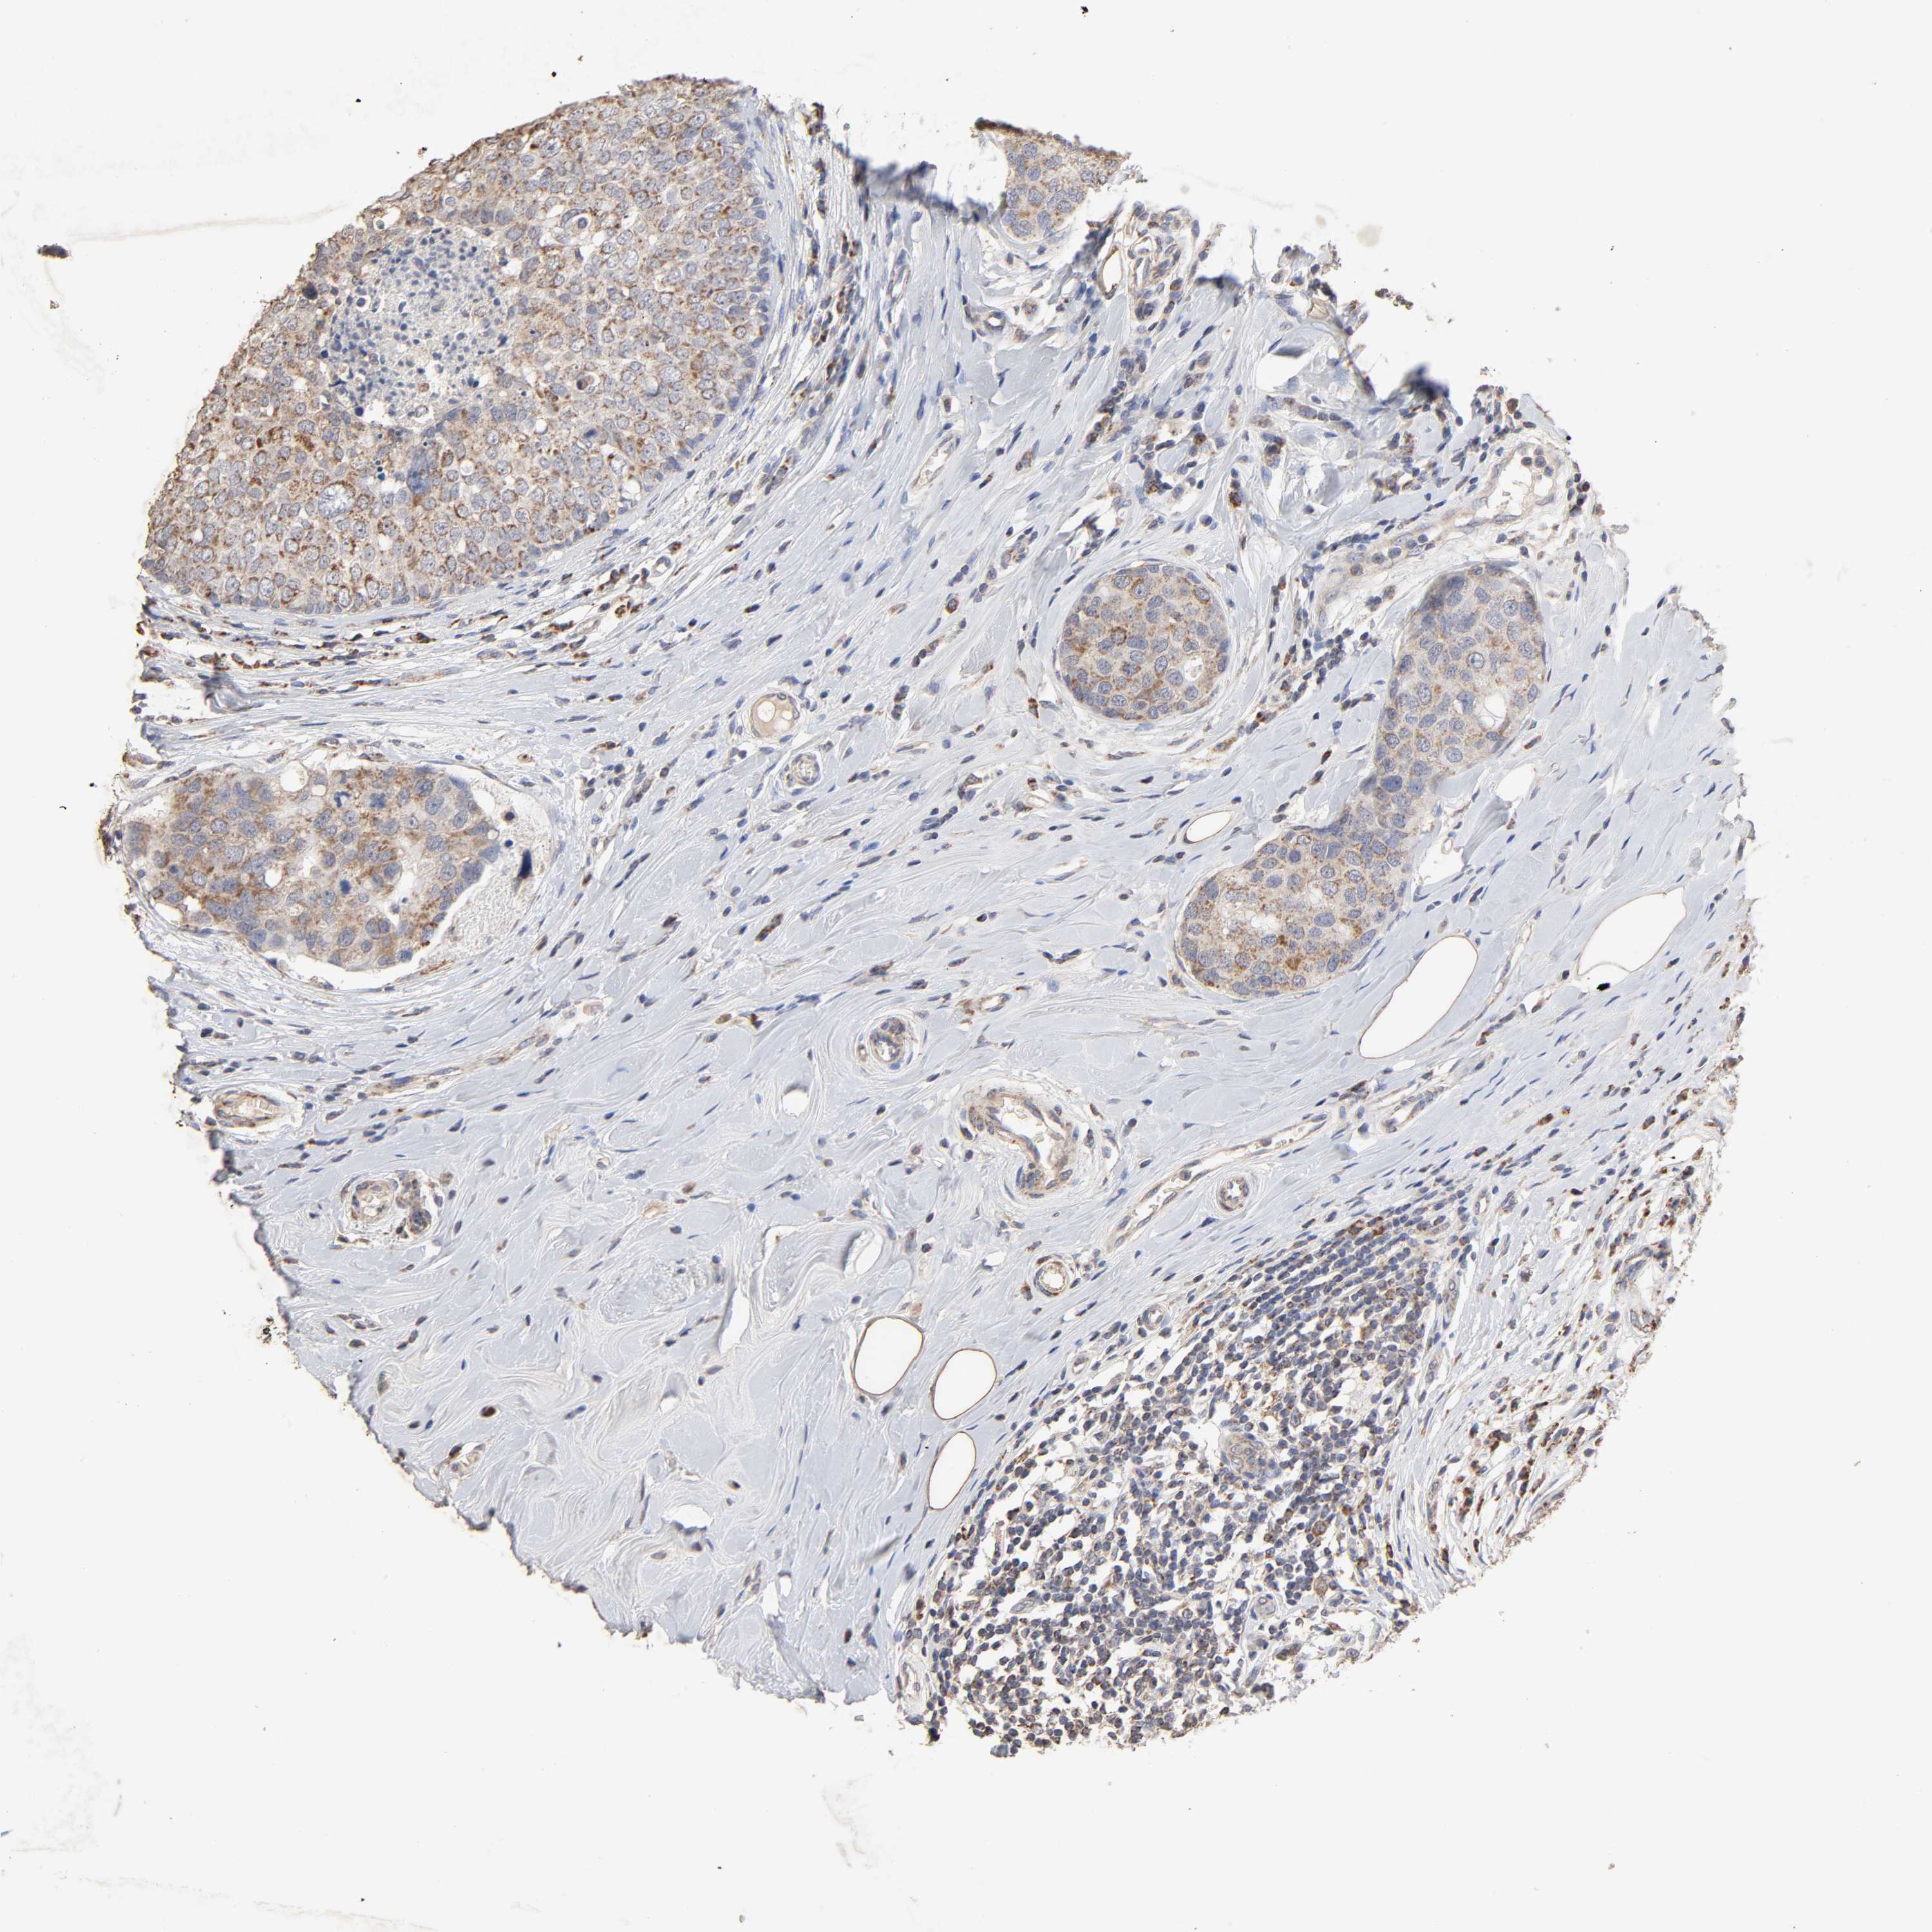

BRCA TCGA BRCA VALIDATION PROTEIN EXPRESSION